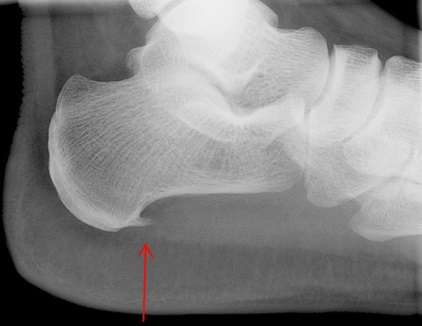

Η παχυσαρκία, η κύηση, η έντονη καταπόνηση στην άθληση, η χρήση παπουτσιών χωρίς καλή υποστήριξη αποτελούν προδιαθεσικούς παράγοντες ανάπτυξης φλεγμονής. Συχνά μπορεί να διαπιστωθεί στην ακτινογραφία του άκρου ποδός η ύπαρξη άκανθας, η οποία συνιστά μια οστέινη προεξοχή σαν αγκάθι στην πτέρνα. Πρόκειται για εναπόθεση αλάτων λόγω χρόνιας υποτροπιάζουσας φλεγμονής της απονεύρωσης. Προκαλεί έντονο πόνο στην όρθια στάση και την βάδιση.